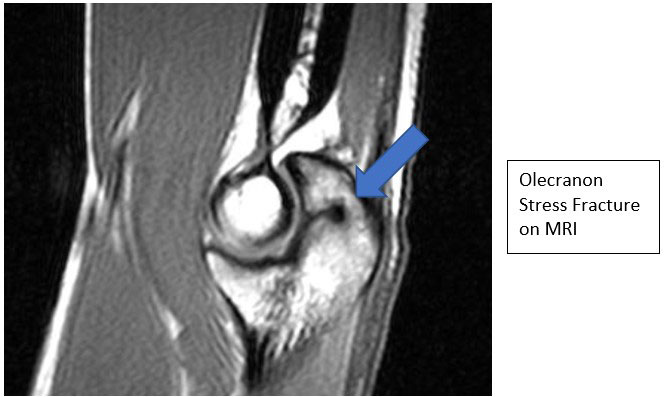

- Radiographs may demonstrate linear sclerosis, fracture lines, or periosteal bone formation. Contralateral films can help determine amount of closure

- MRI, CT and Bone scan can help establish diagnosis if x-rays are normal